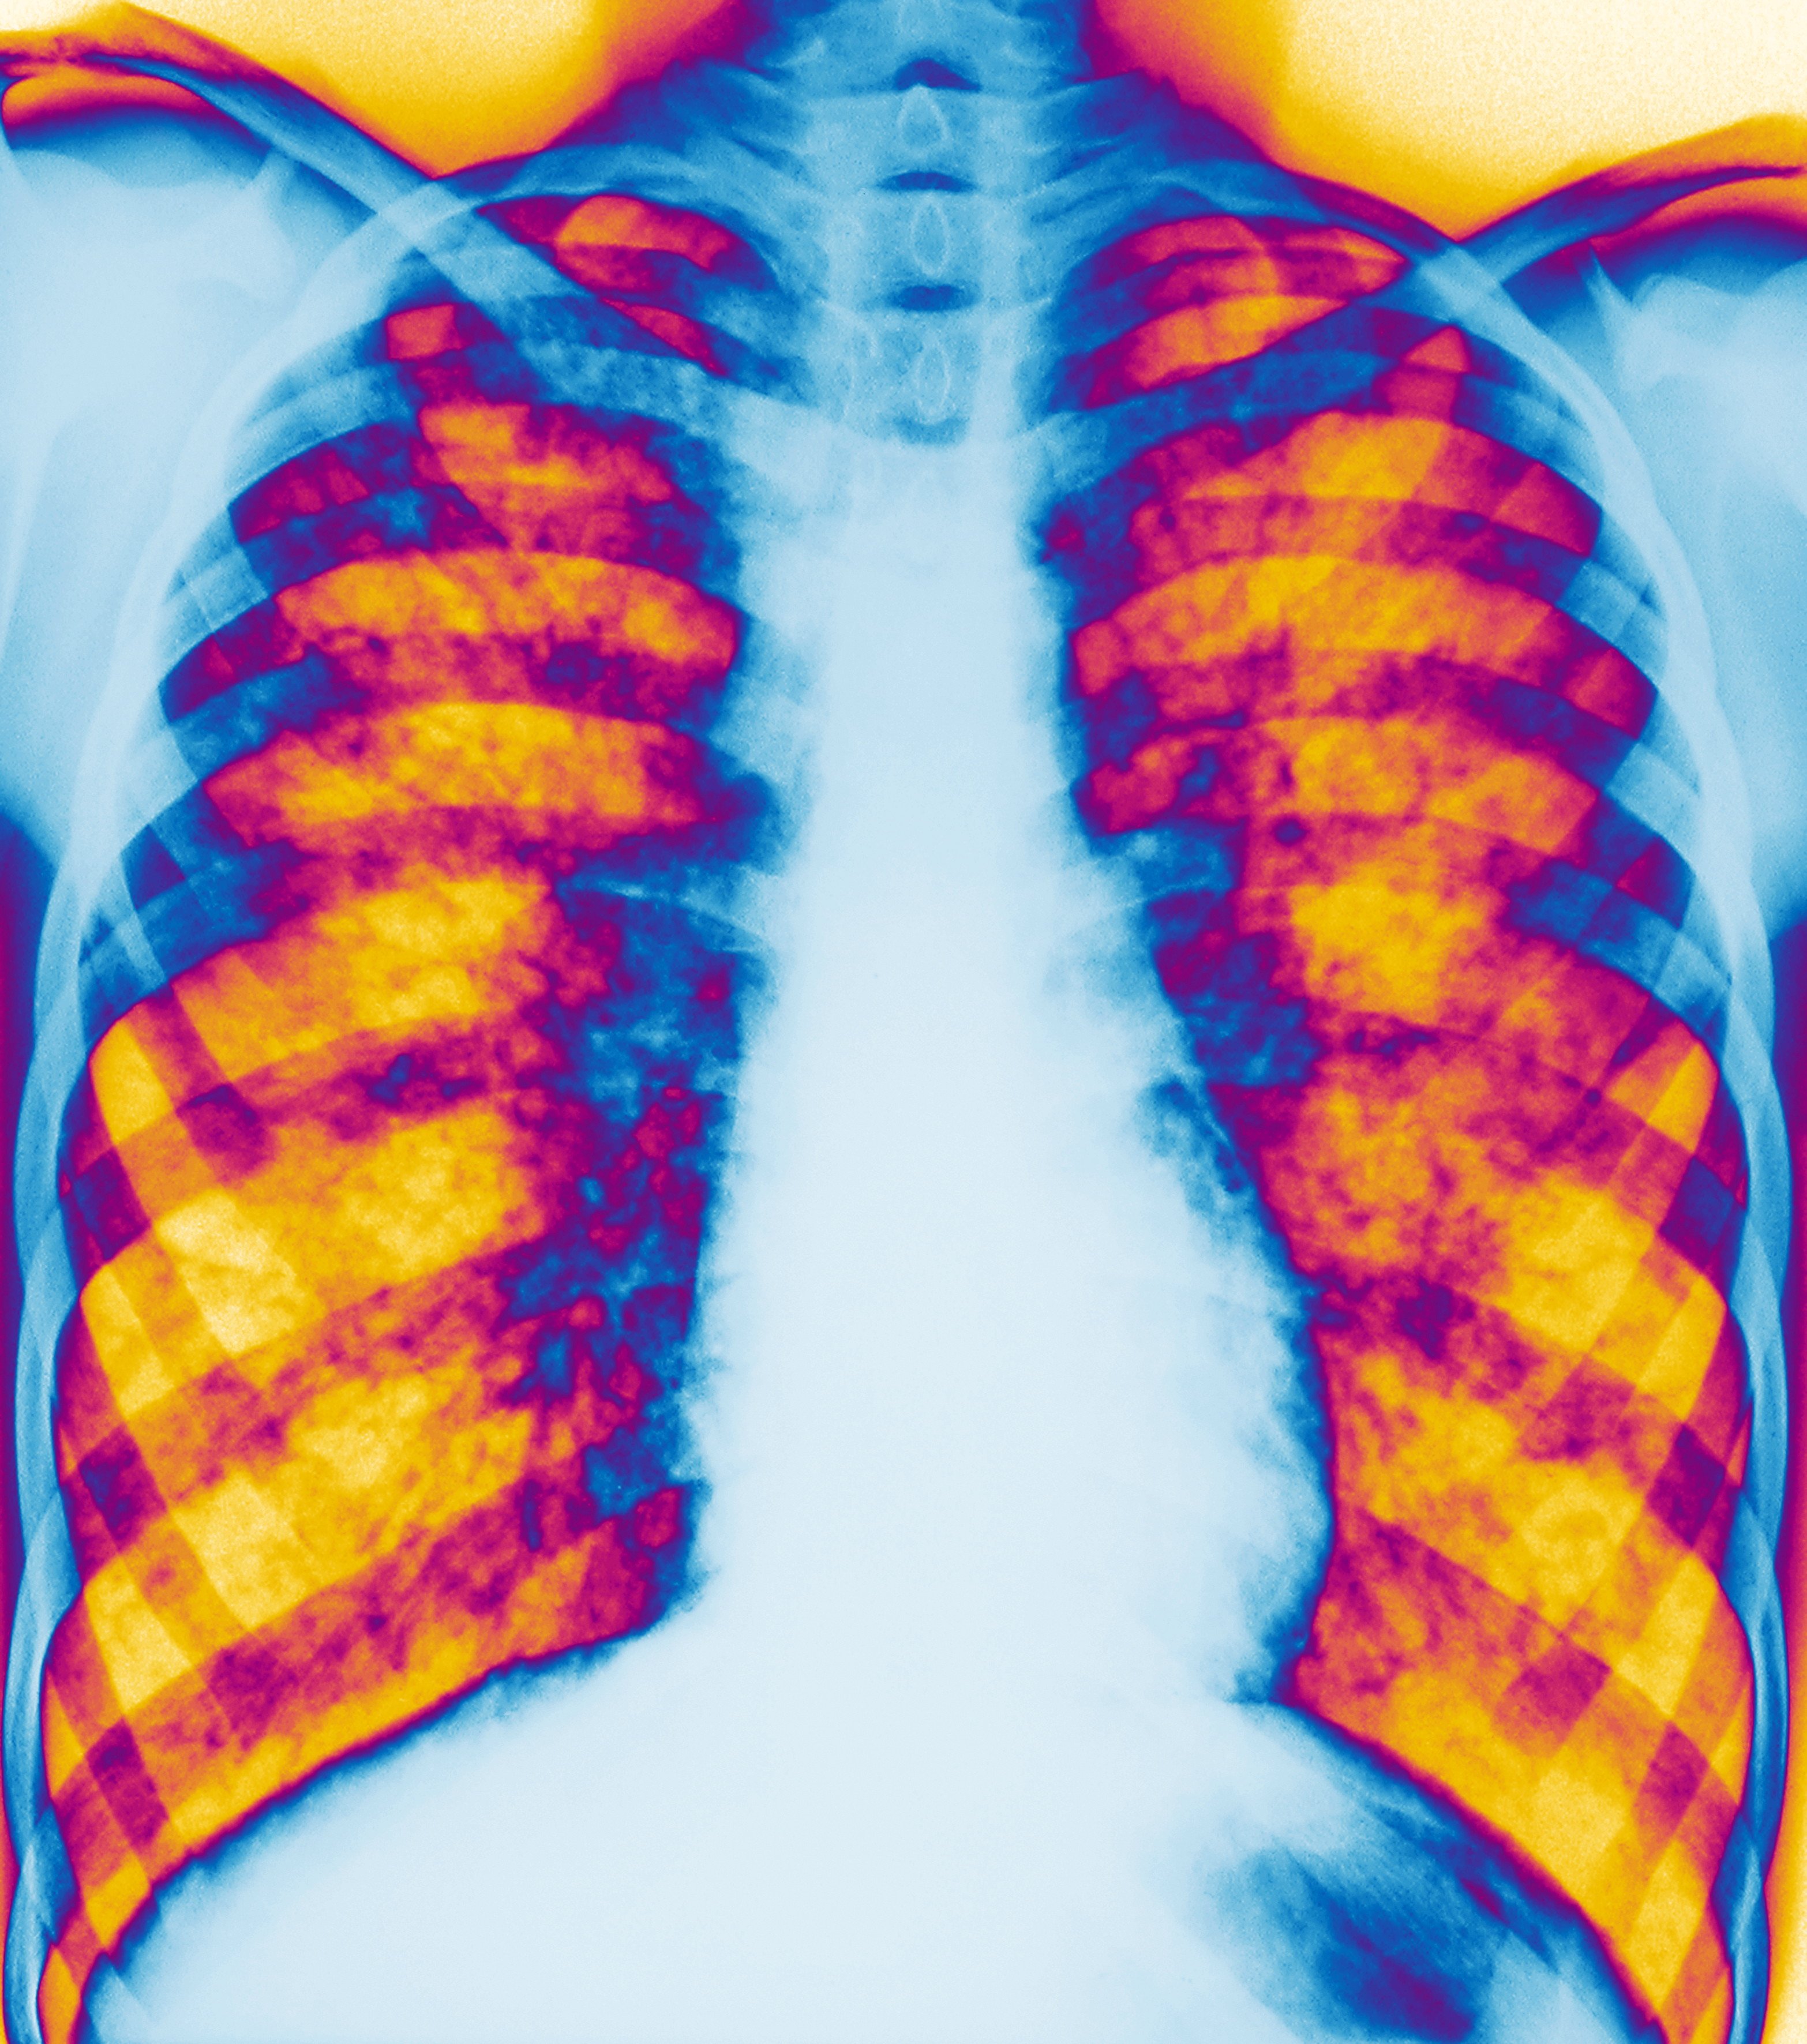

Ova 30-godišnja kopirajterka se bori sa cističnom fibrozom, naslednom genetskom i smrtonosnom bolešću, i to je jedini način da izgura dan, pošto njena pluća rade sa 25 do 35 odsto kapaciteta, a kao posledica ovog oboljenja javili su se osteoporoza i dijabetes.

Kod većine obolelih javljaju se problemi sa plućima, od kojih strada 96 odsto preminulih sa ranije dijagnostifikovanom cističnom fibrozom, ali bolest napada i jetru, bubrege, pankreas, kosti i druge organe, kaže Predrag Minić, specijalista za ovo oboljenje sa Instituta za majku i dete u Beogradu.

Zbog toga organizam luči gustu sluz koja uzrokuje začepljenja i oštećenja organa, a kao posledice javljaju se oboljenja pankreasa, jetre, kostiju i dijabetes, a kod nekih dolazi i do pojave steriliteta, posebno kod muškaraca.

„Nakupljanjem guste, lepljive sluzi u plućima kod osoba sa cističnom fibrozom veća je verovatnoća da će razviti bakterijske infekcije koje mogu trajati kratko vreme“, piše na sajtu cfsrbija.rs.

Bolest uglavnom napada pluća i organe za disanje od čega umire 94 odsto preminulih od cistične fibroze, a četiri odsto strada od bolesti jetre, rekao je doktor Predrag Minić na Okruglom stolu Udruženja za pomoć i podršku osobama sa cističnom fibrozom Srbije.

Ipak, funkcija pluća kod CF pacijenata se u proseku popravila za 10 odsto u poslednjih 10 godina, a sve je veći broj majki sa cističnom fibrozom, tvrdi doktor Minić.